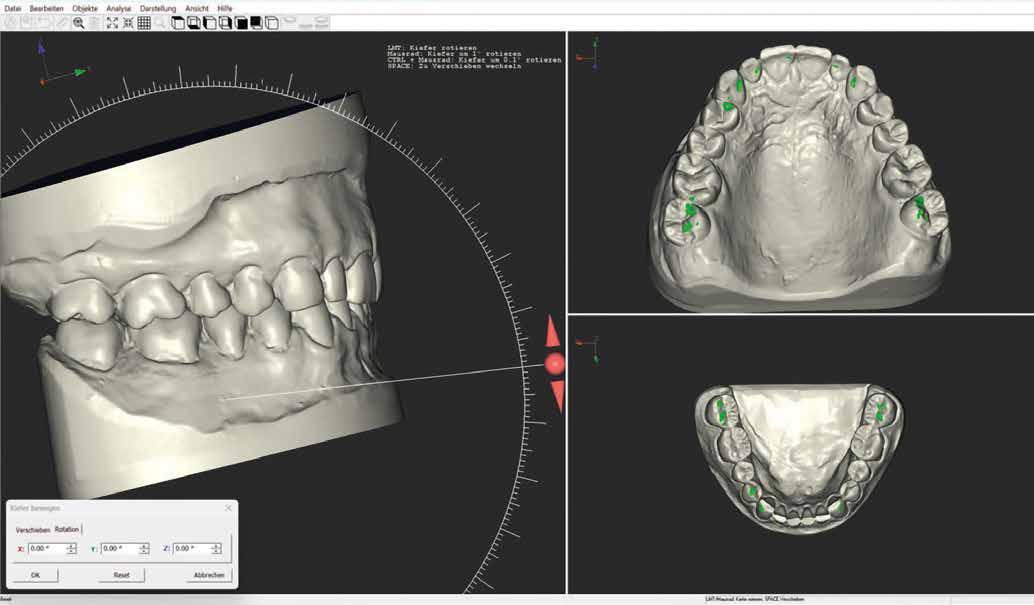

Pácienseset

33 éves páciens konzultált a rendelőben 3 évig tartó fogszabályozása elemeinek eltávolításáról szájából. A kárieszek eltüntetésén kívül optimalizálni szerette volna esztétikai kinézetét. Az első esztétikai elemzés a frontfogak kedvezőtlen hossz-szélesség arányát mutatta (1. kép). A bal felső szemfogat a pulpa elhalása következtében endodonciai kezelésnek is alá kellett vetni.

Klinikai kezelés

A gyökérkezelést és a kárieszek megszűntetését követően kompozittömések készültek, majd preparálták a restaurálandó frontfogakat (3. kép). Ideiglenes koronák is szájba kerültek (4. kép), a jobb kismetszőt meghosszabbították. A fogínylefutás szimmetriáját az ideiglenes koronák megtámasztása segítette. A fogak és íny kívánt szimmetriáját elérve véglegesítették a preparációt (5. kép) és elkészültek a lenyomatok.

ezekre készített mintát és a preparált csonkokkal készült mintát is. A digitális adatállományokat egymásra vetítettük, szeparáltuk a pillérfogakat, a széleket és kontúrokat illesztettük (6–8. képek). Így tökéletesen átvehettük az ideiglenesek formáját. A szubgingivális kontúrokra fókuszáltunk, amelyek megtámasztják a gingivát, hogy a rendelőben ne kelljen majd egyéniesítő utómunkákat végezni. A megtervezett koronákat viasztömbből martuk ki. Erre a célra a ProArt CAD Wax sárga színű tömbjét használtuk (9–10. képek), amely kifejezetten az IPS e.max Press-hez készül. A sima felszínek precíz eredményt hoznak, nagy pontosságú illeszkedéssel karöltve. Az anyag maradék nélkül ég ki. Eddig a pontig maximálisan redukálni tudtuk a manuális munkaráfordítást.

Behelyezés

A fogorvos, fogtechnikus és páciens közötti jó együttműködés kifizetődik, mert a restaurációk a lehető legrövidebb idő alatt, minimális korrekcióval helyezhetők szájba. A klinikai helyzetet, amelyet a mintákon, majd az ideigleneseken keresztül idealizáltunk, a végleges restaurációval is sikerült megvalósítani (13. kép). A páciens és a kezelőcsapat elégedettsége magas szintű volt. A terápia egyenes vonalúnak, sikeresnek bizonyult.

Eredmény

Egy hónap elteltével szép, egészséges képet figyelhettünk meg, ínygyulladás nélkül (14–15. képek). A digi -

tális munkamenet alkalmazása minimális ráfordítással maximális esztétikai eredményt hozott. Az ideiglenes koronák szubgingivális kontúrjának újbóli megvalósítása a végleges pótlással különböző változásokat hozott magával a kezelési folyamat során. Az IPS e.max Press Multi anyag kiemelkedő esztétikai tulajdonságokkal rendelkezik. Ha még ezen felül is egyéniesíteni akarunk, az incizális területet IPS e.max Ceram leplezőkerámiával is kiegészíthetjük (cut-back technika). A bemutatott munkamenet a klasszikus préstechnika kombinálása a számítógép támogatású tervezéssel és gyártással, sok előnyt rejt magában, új kihívásokat jelent, innovatív felhasználást tesz le -